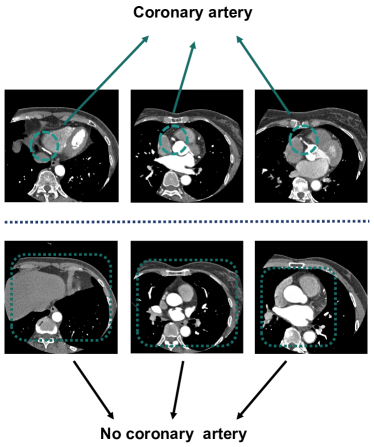

Our evaluation method utilizes a comprehensive set of CCTA datasets. Each dataset consists of between 250 and 320 slices. Due to the completeness of the CCTA scan images, sequence loss is observed in the initial and final portions of the full slice sequence, as illustrated in Figure 5. We present a selection of representative slices from the original CCTA.Given the complex structure of coronary vessels and the presence of substantial noise interference, only the upper half of the CCTA is discernible, while the lower half is not. Therefore, this study focuses solely on Computed Tomography Angiography images that include coronary arteries. Through manual screening, a total of 848 CCTA images were selected for this study. Each image measures 600 600 pixels.The CCTA data was divided into a training set, randomly selected from six patients’ data, and a test set, comprising the remaining data.